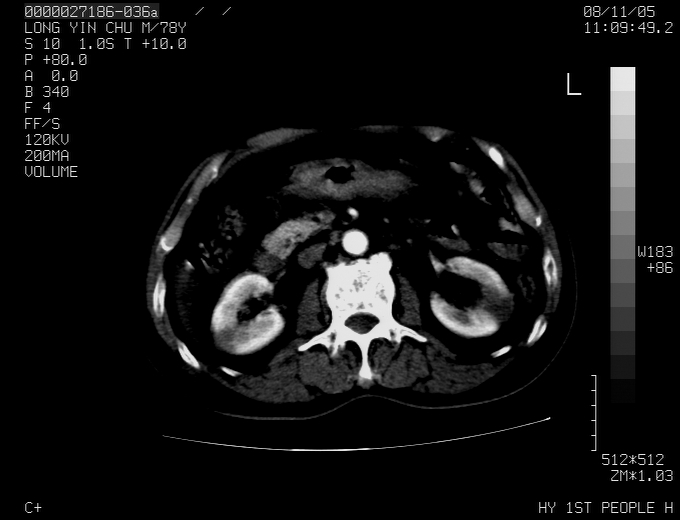

标题: CT16532:M78Y,肝脏病变,请会诊 [打印本页]

标题: CT16532:M78Y,肝脏病变,请会诊

腹胀,腹痛就诊,男性,78岁,外院b超未见异常。

肝ca,脾肾转移

考虑弥漫性肝癌并脾及双肾转移.双侧胸水.

图片质量欠佳:多考虑:左侧肾癌。脾脏转移!胸膜转移!

肝脾肾转移瘤可能性大,左肾不除外梗塞,双侧胸水

考虑弥漫性肝癌并脾及双肾转移,双侧胸水。